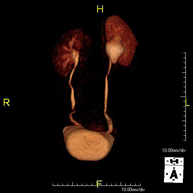

Prova diagnòstica no invasiva que consisteix en l'obtenció d'imatges d'alta definició anatòmica del fetge mitjançant l'ús d'un camp electromagnètic i ones de ràdio (amb un emissor i un receptor). No utilitza radiació ionitzant. Es realitza per estudiar qualsevol lesió localitzada en el fetge. Normalment es requereix l'ús de contrast paramagnètic (Gadolini) per caracteritzar les lesions. És necessari realitzat la prova en dejú (6 hores). - RM de Ronyons

Prova diagnòstica no invasiva que consisteix en l'obtenció d'imatges d'alta definició anatòmica d'ambdós ronyons mitjançant l'ús d'un camp electromagnètic i ones de ràdio (amb un emissor i un receptor). No utilitza radiació ionitzant. Es realitza per estudiar qualsevol lesió localitzada en ambdós ronyons. Normalment es requereix l'ús de contrast paramagnètic (Gadolini) per caracteritzar les lesions. - RM de Glàndules Suprarenals

Prova diagnòstica no invasiva que consisteix en l'obtenció d'imatges d'alta definició anatòmica de les dues glàndules suprarenals mitjançant l'ús d'un camp electromagnètic i ones de ràdio (amb un emissor i un receptor). No utilitza radiació ionitzant. No necessita preparació prèvia. No requereix l'ús de contrast paramagnètic (Gadolini). Està especialment indicada en aquells pacients en els quals és imprescindible diferenciar el nòdul suprarenal benigne (l'adenoma suprarenal és el més freqüent) d'altres lesions suprarenals (tant benignes -hematomes, angiomiolipomas, etc.- com malignes). - RM de Melsa

Prova diagnòstica no invasiva que consisteix en l'obtenció d'imatges d'alta definició anatòmica de tot el cos mitjançant l'ús d'un camp electromagnètic i ones de ràdio (amb un emissor i un receptor). No utilitza radiació ionitzant. És una prova molt important en la recerca de metàstasi en pacients amb neoplàsia coneguda. No requereix preparació prèvia. No és necessari l'ús de contrast paramagnètic (Gadolini). - Angio-RM d'Aorta abdominal